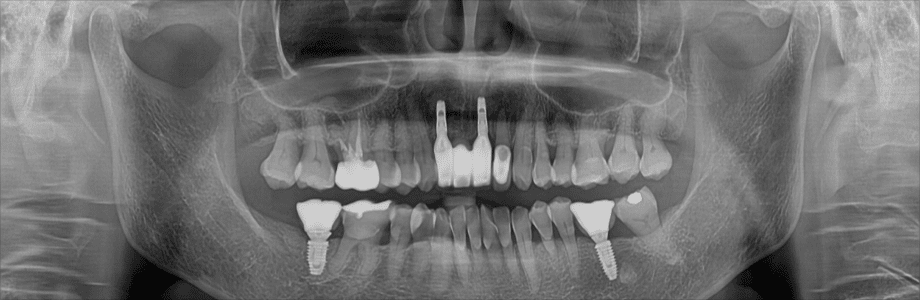

가이드 수술